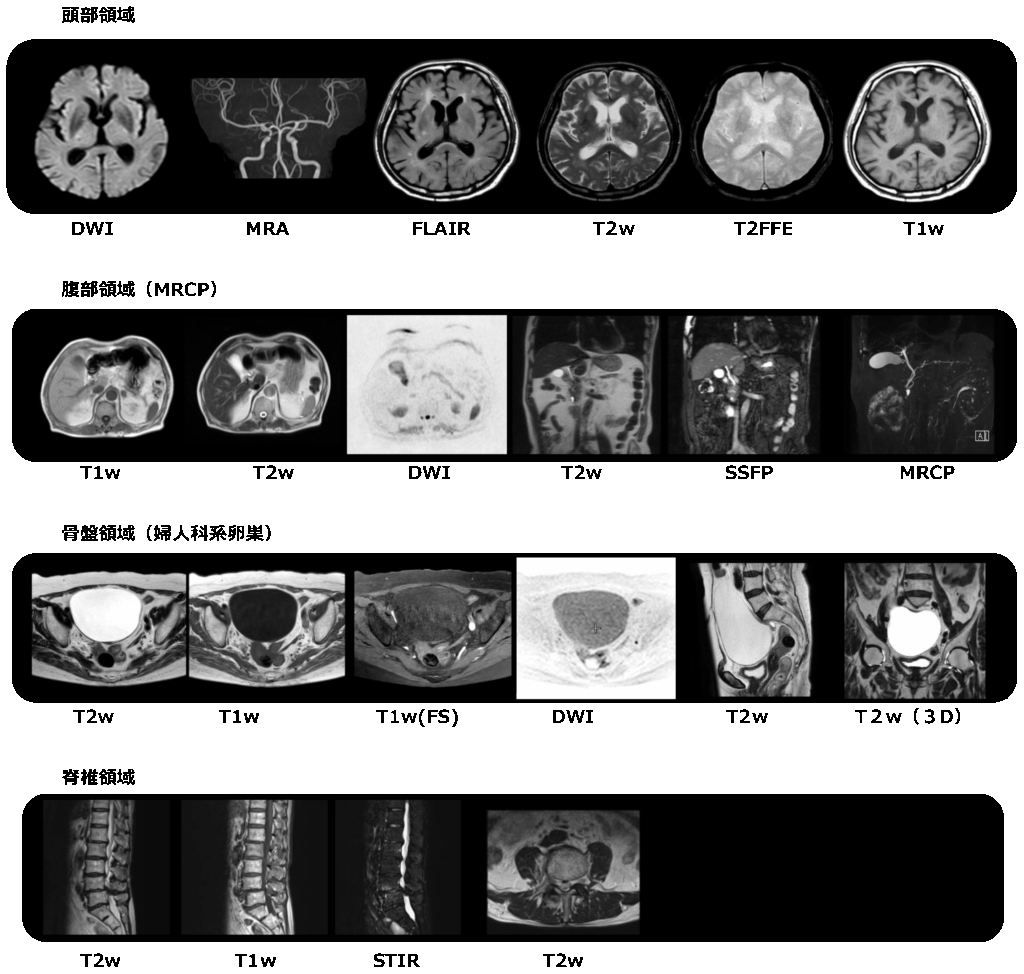

画像の例